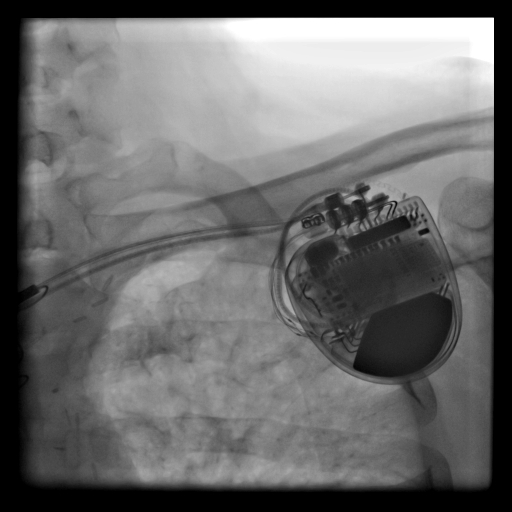

İleri Kalp yetersizliği olan hastalarda “VF” denen öldürücü ritm bozukluğu meydana gelmektedir. Kalp yetersizliği bulunan hastalara implante edilen (takılan) ve ” ICD” olarak bilinen kalp pilleri ölümcül seyreden bu ritmi normal ritme çevirerek hasta ölümünü engelleyebilmektedir

ICD, köprücük kemiğinin hemen altına cilt açılarak yerleştirilir. Pile ait elektrot kablolar ise toplardamar üzerinden sağ kalp içine yerleştirilir. Bu kablolar tehlikeli bir çarpıntı oluştuğunda onları algılar ve pile iletir, sonuçta pil elektro şok diyebileceğimiz tedavi edici akım vererek çarpıntıyı düzeltir. İşlem yaklaşık ½ saat sürer, lokal anestezi ile gerçekleştirilir.

- Öldürücü Ritmi Önleyen Pil (ICD)

- Öldürücü Ritmi Önleyen ve Kalp Fonksiyonlarını İyileştiren Çift Odacıklı Pil Tedavisi (CRT)